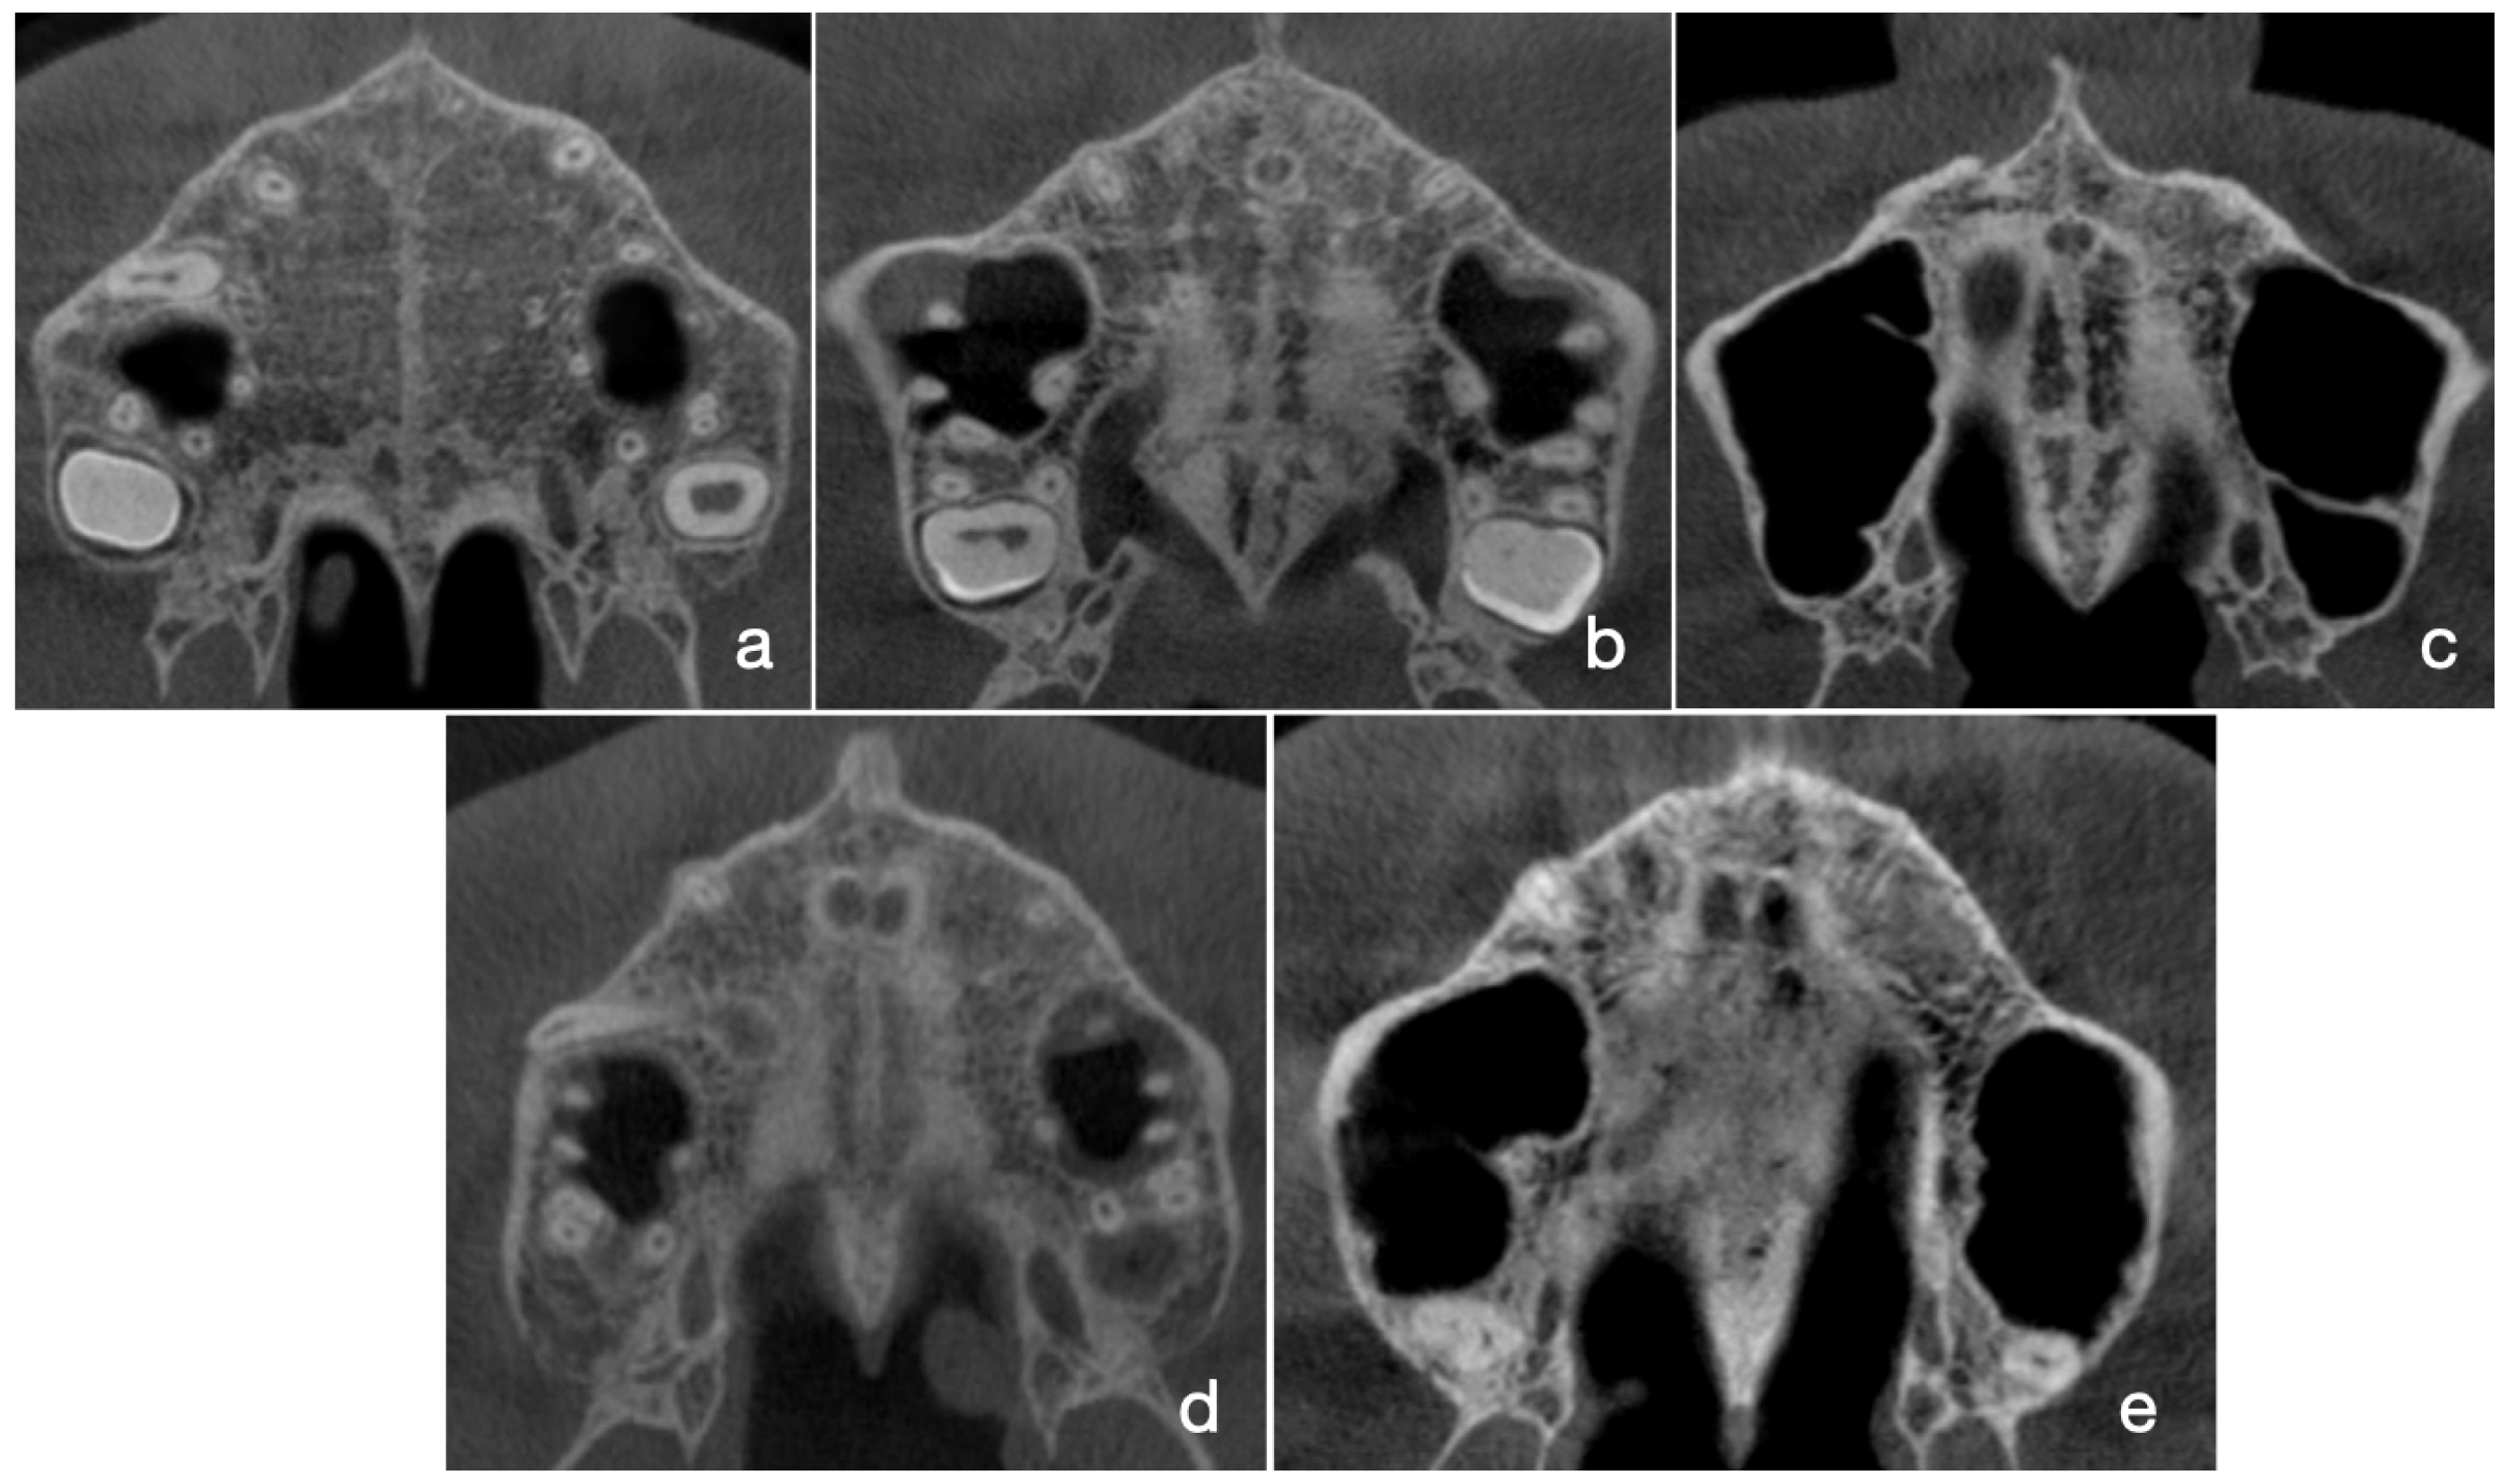

2.3. Assessment of MPS Maturation Stages According to Angelieri’s Classification Method

- Angelieri, F.; Cevidanes, L.H.; Franchi, L.; Gonçalves, J.R.; Benavides, E.; McNamara, J.A., Jr. Midpalatal suture maturation: Classification method for individual assessment before rapid maxillary expansion. Am. J. Orthod. Dentofac. Orthop. 2013, 144, 759–769. [Google Scholar] [CrossRef]